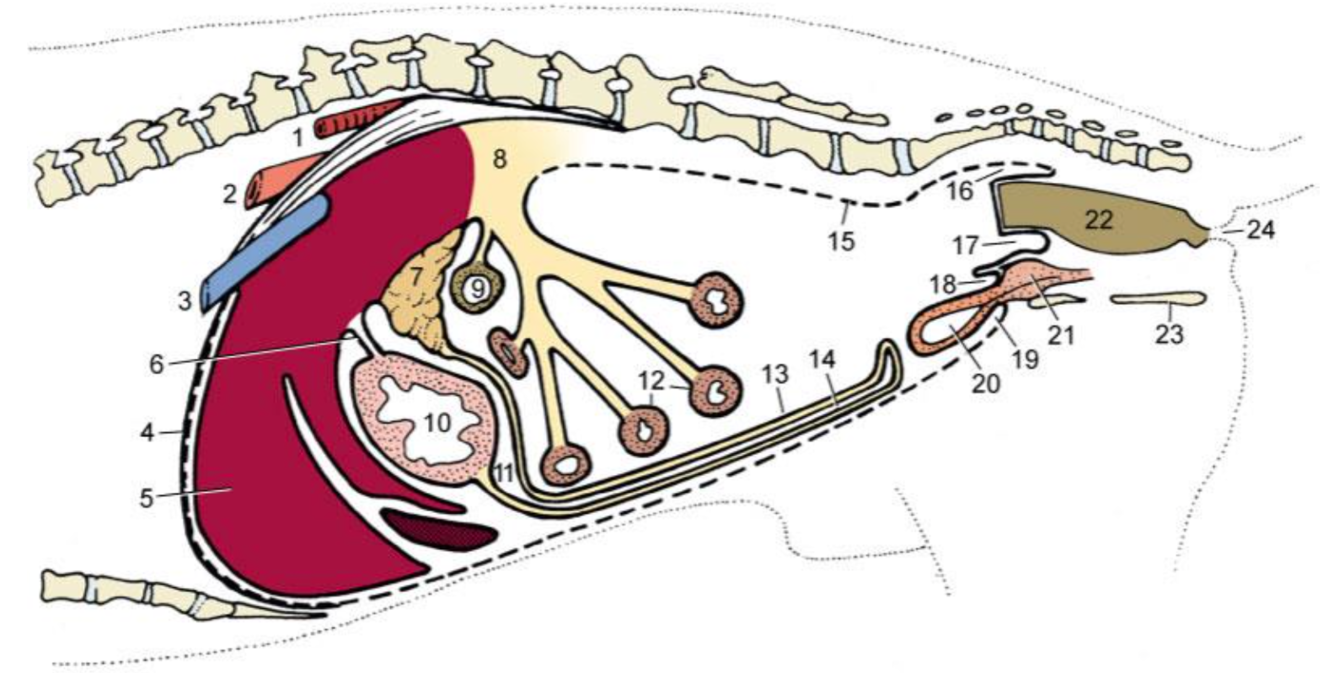

Runs caudally (right side) – Descending duodenum- level of tuber coxae- makes a U- turn –runs obliquely-craniosinistrally (leftside)- continues as the ascending duodenum

Re. Cranial duodenum, topographical position?

Dorsally and laterally lies in contact with the liver and medially by the pancreas

Re. jejunum. topography? structure? blood supply?

Confined to the ventral part of the abdomen

Fan shaped mesentry – mesentric surface & antimesentric

Blood supply –branches of the cranial mesenteric artery

Re. 3 regions of colon. topography?

ascending colon - right side

transverse - colon cranial to the root of mesentery (right side)

descending colon - left side